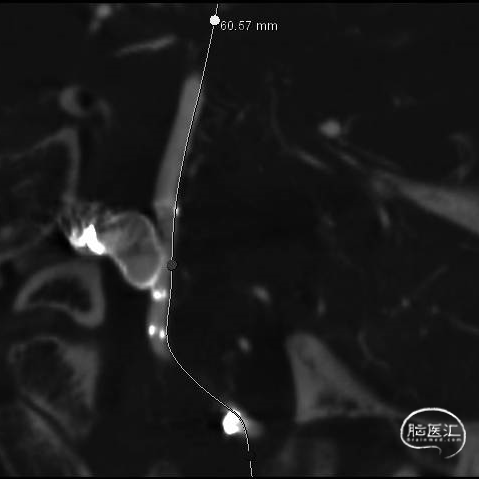

经测量可得动脉瘤宽度平均值为7.0mm,动脉瘤高度为7.4mm,最终选择WEB™ SL 9*6。

动脉瘤远端子囊先进行填圈,近端动脉瘤植入WEB™。

术后6个月影像提示血栓形成,动脉瘤完全闭塞,WEB™完全栓塞。